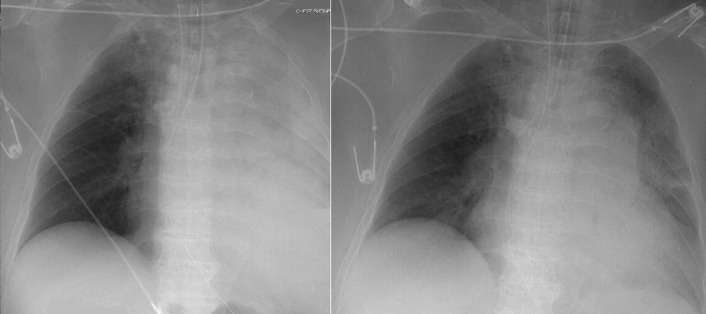

Complications of intubation ( Figs. 25-1 to 25-10 ) and ventilation that are apparent on a chest radiograph are often potentially life-threatening and should be excluded on every radiograph, both immediately following intubation and with each subsequent radiograph. These possibilities are listed in the following sections.

Right Mainstem Bronchus Intubation

Possible overinflation of the right lung

Possible volume loss of the left lung